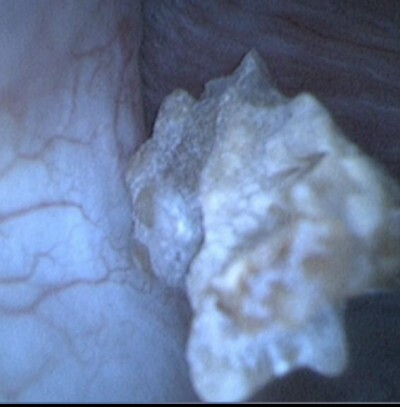

▲ 謝小姐的結石大小不到一公分,卻因在腎臟與輸尿管間來回,導致反覆發炎(圖/光田醫院提供)

光田綜合醫院泌尿科主治醫師丁原田醫師解釋,謝小姐的困境並非孤例,因為有時候結石的位置較高,且介在腎臟與輸尿管之間,容易在兩邊來回移動,使得傳統的輸尿管鏡手術難以準確定位和取石。當結石又一次「頑強」地移回腎臟深處時,一般的輸尿管鏡就會「夾不出」,讓醫師和患者陷入苦戰。為了解決這個難題,丁醫師運用了可彎曲的軟式輸尿管鏡,成功地將結石一夾而出,讓謝小姐終於擺脫了痛苦。